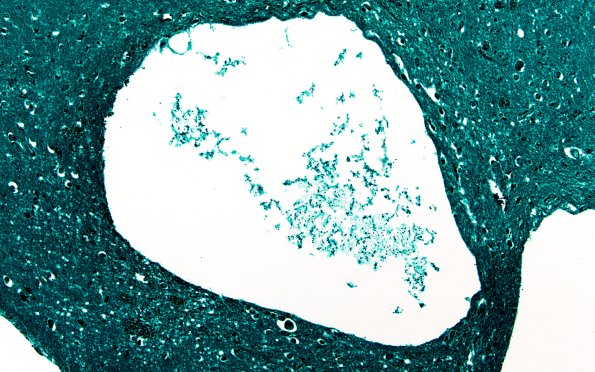

Washington University Experience | BASIC PROCESSES | Artifacts | Artifact - Swiss Cheese Brain | 34D1A Swiss Cheese Brain (Case 12) GMS 20X 2

34D1,2 Although GMS stain is typically used for fungal organisms, it labels bacteria as well. (GMS)